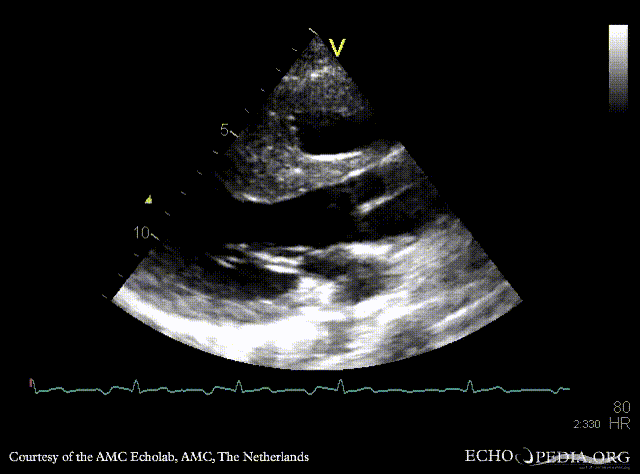

| A4CH

A4CH: color Doppler of AV valve regurgitation